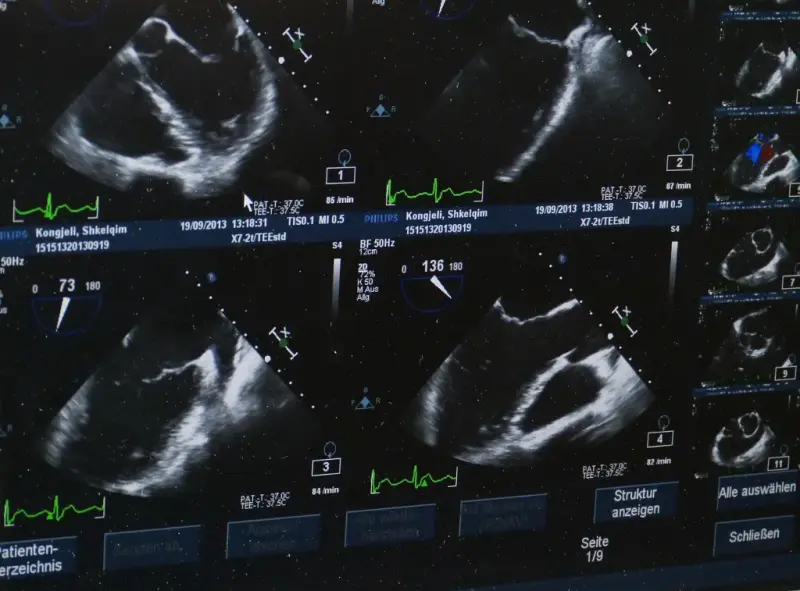

aparat usg